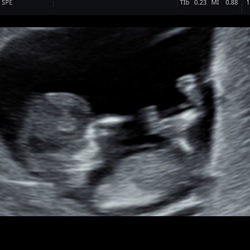

Ik had wel een echo gekregen om te kijken of het goed zat. Met 6 weken was er een zwarte vlek te zien waardoor ze wisten dat het vruchtje nog in mij zat, ze konden zien of het bij het termijn qua groei paste.